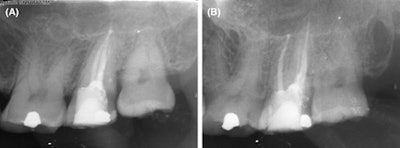

(A) Patient x-ray immediately after surgery. (B) Patient x-ray one year after surgery.